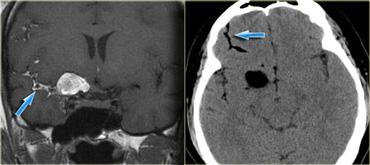

Bên trái là ba tổn thương ngấm thuốc dạng vòng khác nhau.